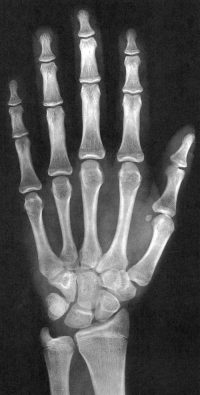

Sexo Masculino

11 anos